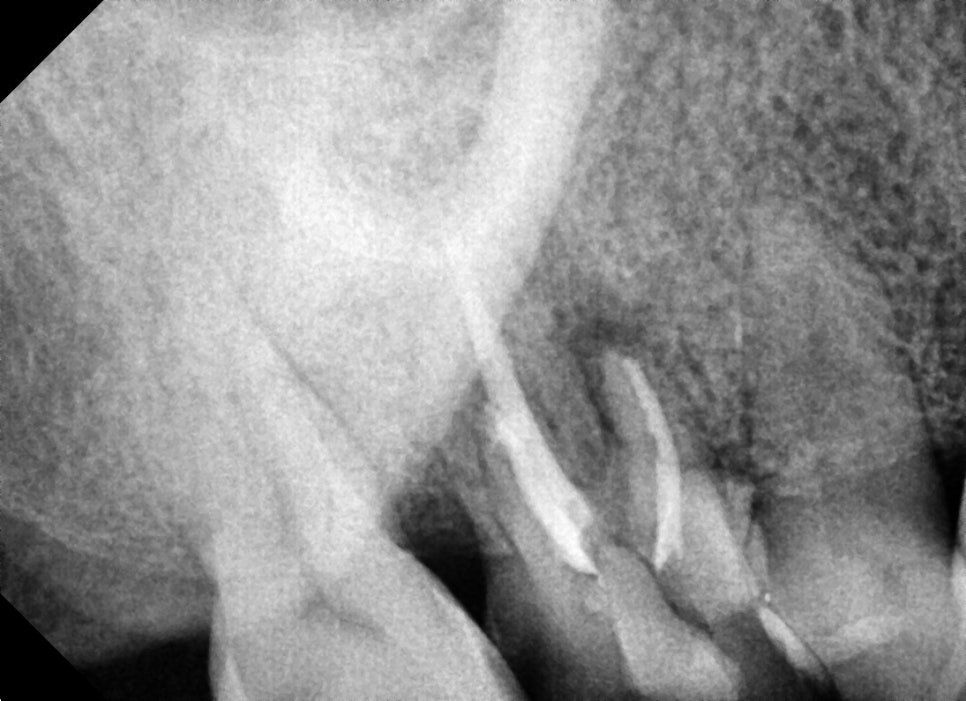

신경관 내 충전재의 길이를 사진 찍어가며 확인하고 신경치료를 마무리 한 사진입니다.

뿌리가 총 3개인데 3개의 신경관 모두 염증이 심하셨지만 최대한 소독하고 증상이 없는 상태에서 마무리하고